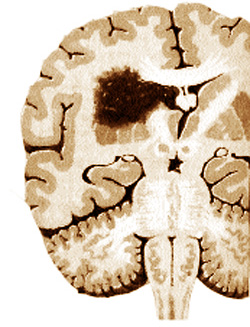

2. Apoi rapid această arteră care a fost supusă vasoconstricţiei se dilată şi fluxul sanguin se amplifică antrenând o adevărată congestie locală – faza de vasodilataţie (foto 2). Acum apare durerea, surdă sau pulsatilă (precum loviturile de ciocan). Dacă apar manifestări digestive (greaţă său vomă), ele sunt consecinţă iritării unui anumit centru cortical şi nu sunt legate de o tulburare digestivă.

3. Urmează, în final, faza de edem, (foto 3) în care se produce o inhibiţie a pereţilor arterelor scalpului şi o infiltraţie edematoasă cerebrală (difuziunea sângelui prin pereţii vaselor în ţesutul nervos), care explică instalarea somnolenţei, a apatiei şi oboselii spre sfârşitul atacului de migrenă.